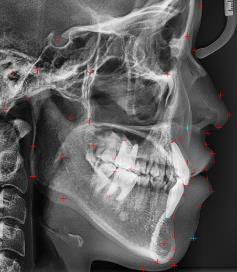

自動Ceph分析軟體

利用影像處理技術和深度學習算法技術,結合人工智慧功能的數位牙科解決方案就在這。

透過人工智慧化的牙齒診斷和診療計劃,可以有效地進行診療,能夠節省時間和費用,請在矯正前先確認"Before和After"的模樣吧!